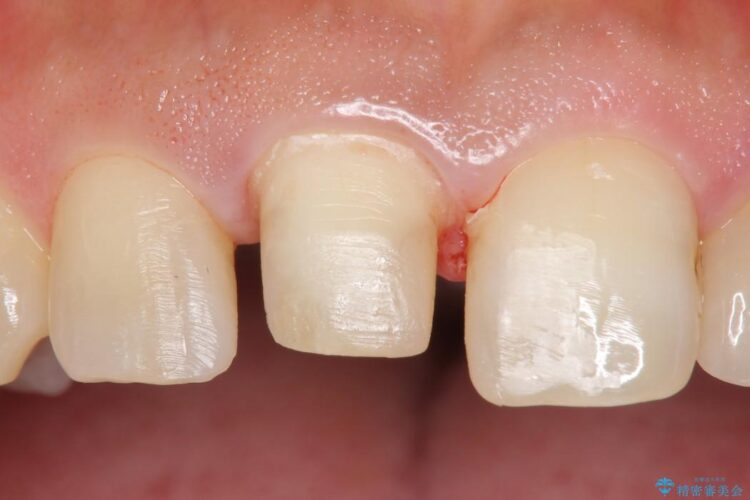

今回のケースでは丁寧に虫歯を取りきることにより、神経を保存することができました。

虫歯は早期発見・治療ができれば患者様への負担も軽く歯を長持ちさせることができますので、定期検診や異変を感じたらなるべくお早めに歯科医院へ行かれることをお勧めいたします。